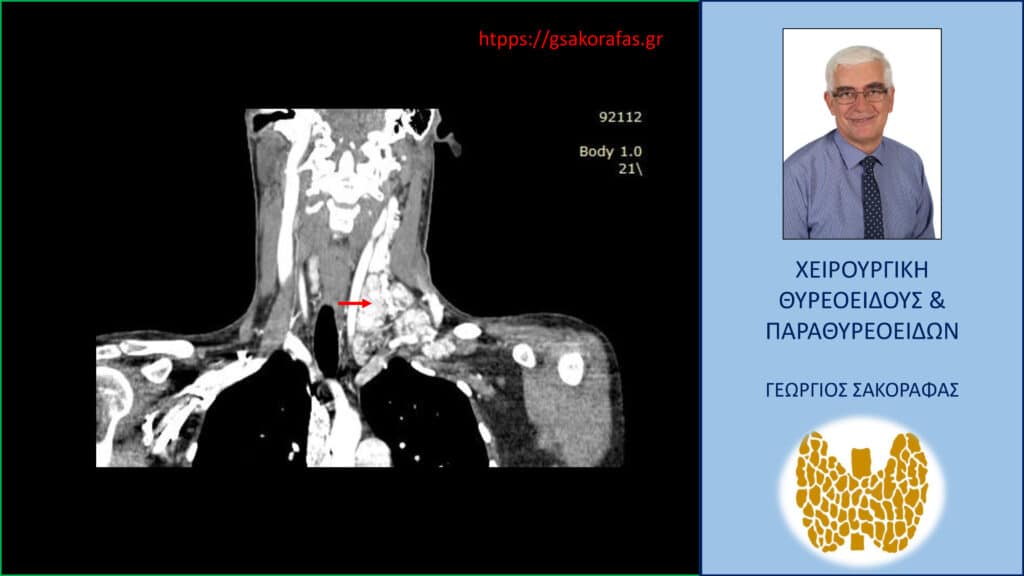

- Γιατί είμαστε σε θέση να εκτελέσουμε με ασφάλεια και αποτελεσματικότητα κάθε είδους χειρουργική επέμβαση θυρεοειδούς – παραθυρεοειδών, ακόμη και σε επιπλεγμένα (δύσκολα) περιστατικά, όπως εκτεταμένοι λεμφαδενικοί καθαρισμοί σε καρκίνο θυρεοειδούς, επεμβάσεις σε λίαν ευμεγέθεις καταδυόμενες στο μεσοθωράκιο βρογχοκήλες, υποτροπές παθήσεων θυρεοειδούς (συμπεριλαμβανομένου του καρκίνου θυρεοειδούς), υποτροπές υπερπαραθυρεοειδισμού, αδενώματα παραθυρεοειδών σε έκτοπη θέση ή λόγω υπεράριθμων παραθυρεοειδών, διάχυτη υπερπλασία παραθυρεοειδών, κλπ.